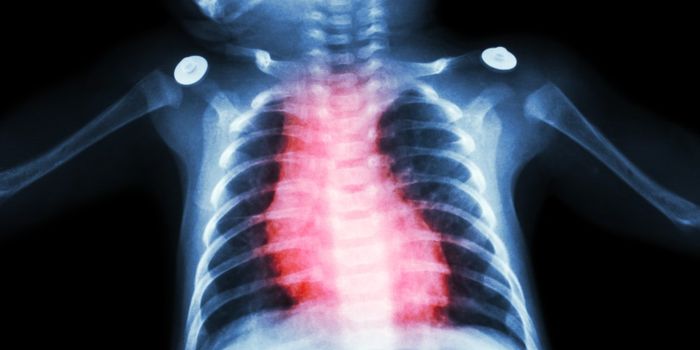

Read the latest articles about newly released neuroscience research and advances in experimental techniques. Topics include research news in neuroscience, neurology, psychology, brain science and cognitive sciences.